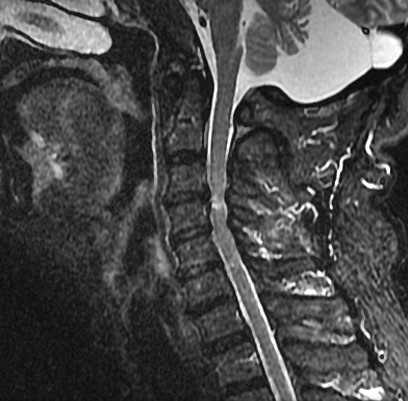

而“脊髓型颈椎病”,指的就是由于颈椎的退行性改变(如椎间盘突出、骨质增生、韧带肥厚等),导致颈椎管这个“隧道”变得狭窄,直接压迫甚至损伤了其中的“高速公路”——脊髓。当脊髓受压后,其指挥四肢运动、传递感觉信号的功能就会发生障碍。

这就不难理解,为什么杨大爷会出现双腿无力、行走不稳、有“踩棉花感”这些症状。因为控制下肢运动的“指令”在“上游枢纽”就被卡住了,无法准确传达到腿部肌肉。这绝不是简单的“年老体衰”,而是神经系统发出的明确警报!

当杨大爷得知需要手术时,他和家人最初都非常紧张和抗拒。这是人之常情。但医生建议手术,是基于一个至关重要的医学共识:对于确诊的、有症状的脊髓型颈椎病,手术是唯一被证实有效的根治性治疗方法。

1.脊髓损伤不可逆:脊髓神经细胞非常娇嫩,一旦因长期受压而发生变性、坏死,其功能是难以恢复的。药物、理疗、按摩等保守治疗,无法解除对脊髓的机械压迫,甚至不当的按摩还可能加重病情,导致瘫痪。

2.手术的目的是“减压”:手术如同为被堵的“高速公路”进行“拓宽清障”。医生会通过微创或开放手术,移除压迫脊髓的椎间盘、骨赘或肥厚的韧带,为脊髓松绑,恢复其赖以生存的空间和血供。